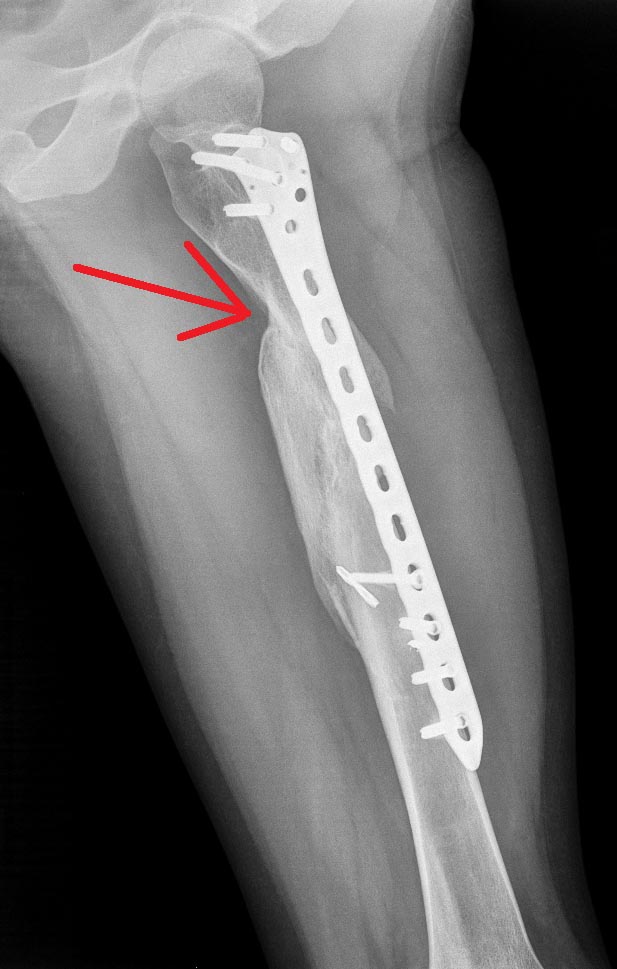

Пациентка 24 г. Травма 2 года назад, операция- малоинвазивный

остеосинтез бедренной мыщелковой пластиной. В настоящий момент пациентка

намерена удалить пластину (мешает).

Смущает участок, отмеченный стрелкой- выдержит ли полную нагрузку. Стоит

ли удалять пластину? Спасибо!